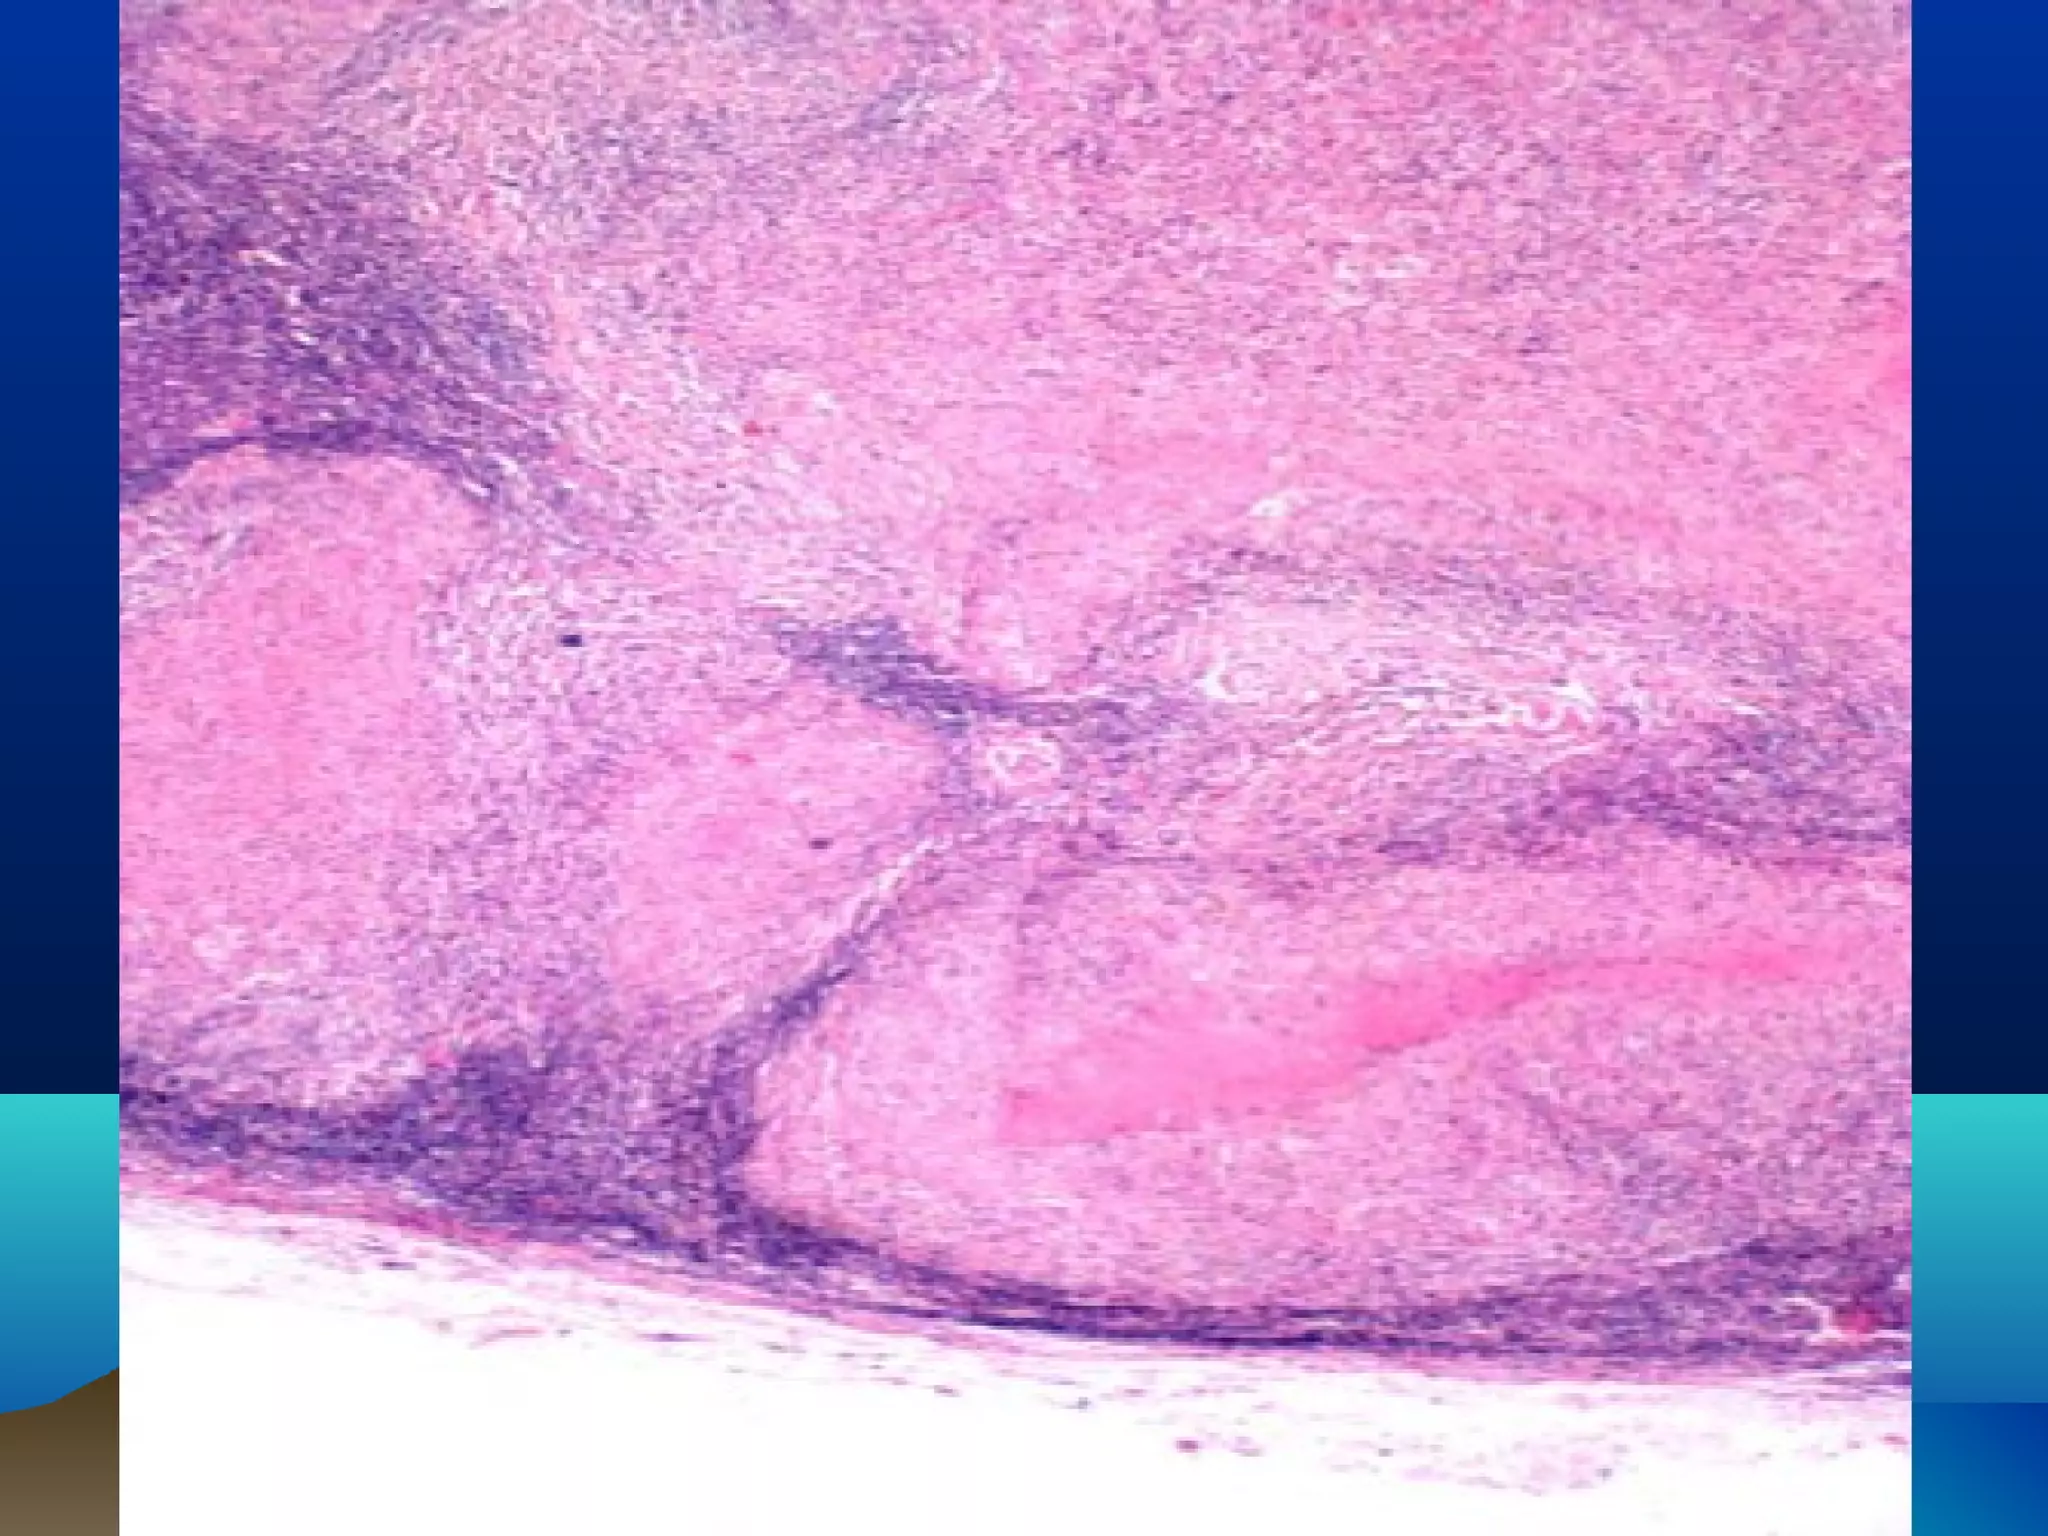

Spleen; Coagulative necrosis

• The microscopy is distinctive. After loss of their

nuclei, the cytoplasm of the cells remains intact for

days. The "tombstones" reveal the structure of the

living tissue. If the patient lives, the edges of the

necrotic area become inflamed, and eventually the

dead cells will be removed by white blood cells

• RULE: Unless otherwise specified in this section,

the death of a group of cells will result in

coagulation necrosis

• (Ischemic necrosis=Infarction)

Kidney infarct exhibiting coagulative necrosis, with loss of nuclei

and clumping of cytoplasm but with preservation of basic outlines

of glomerular and tubular architecture